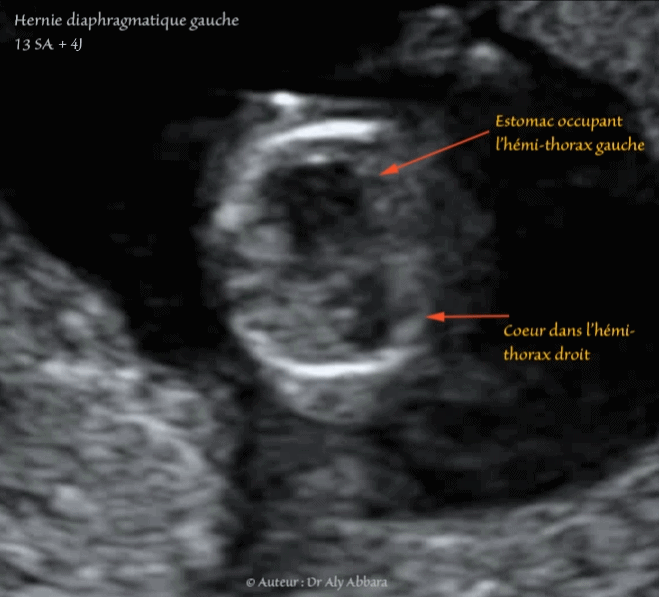

Echographie Hernie Diaphragmatique Exencephalie 13 14 Sa فتق الحجاب الحاجز الأيسر ا نعدام الجمجمة